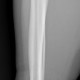

Saya cukup bingung dok untuk menentukan garis fraktur pada os tibia pasien, apakah ini termasuk fraktur inkomplit dok? Karena saya tidak melihat diskontinuitas tulang sejelas saya melihat diskontinuitas pada fibula

Alo dokter, fragmen tibia ada di distal melibatkan metafisis dan epifisis, ini termasuk fraktur intraartikuler

Alo dokter, setuju dengan pendapat dr.Yohannes Toban, saya melihat adanya garis fraktur pada bagian distal tibia daerah yang kita sebut dengan tibial plafond (pilon), dan medial maleolus nya. Baiknya supaya lebih jelas, boleh menambahkan rontgen Ankle joint.